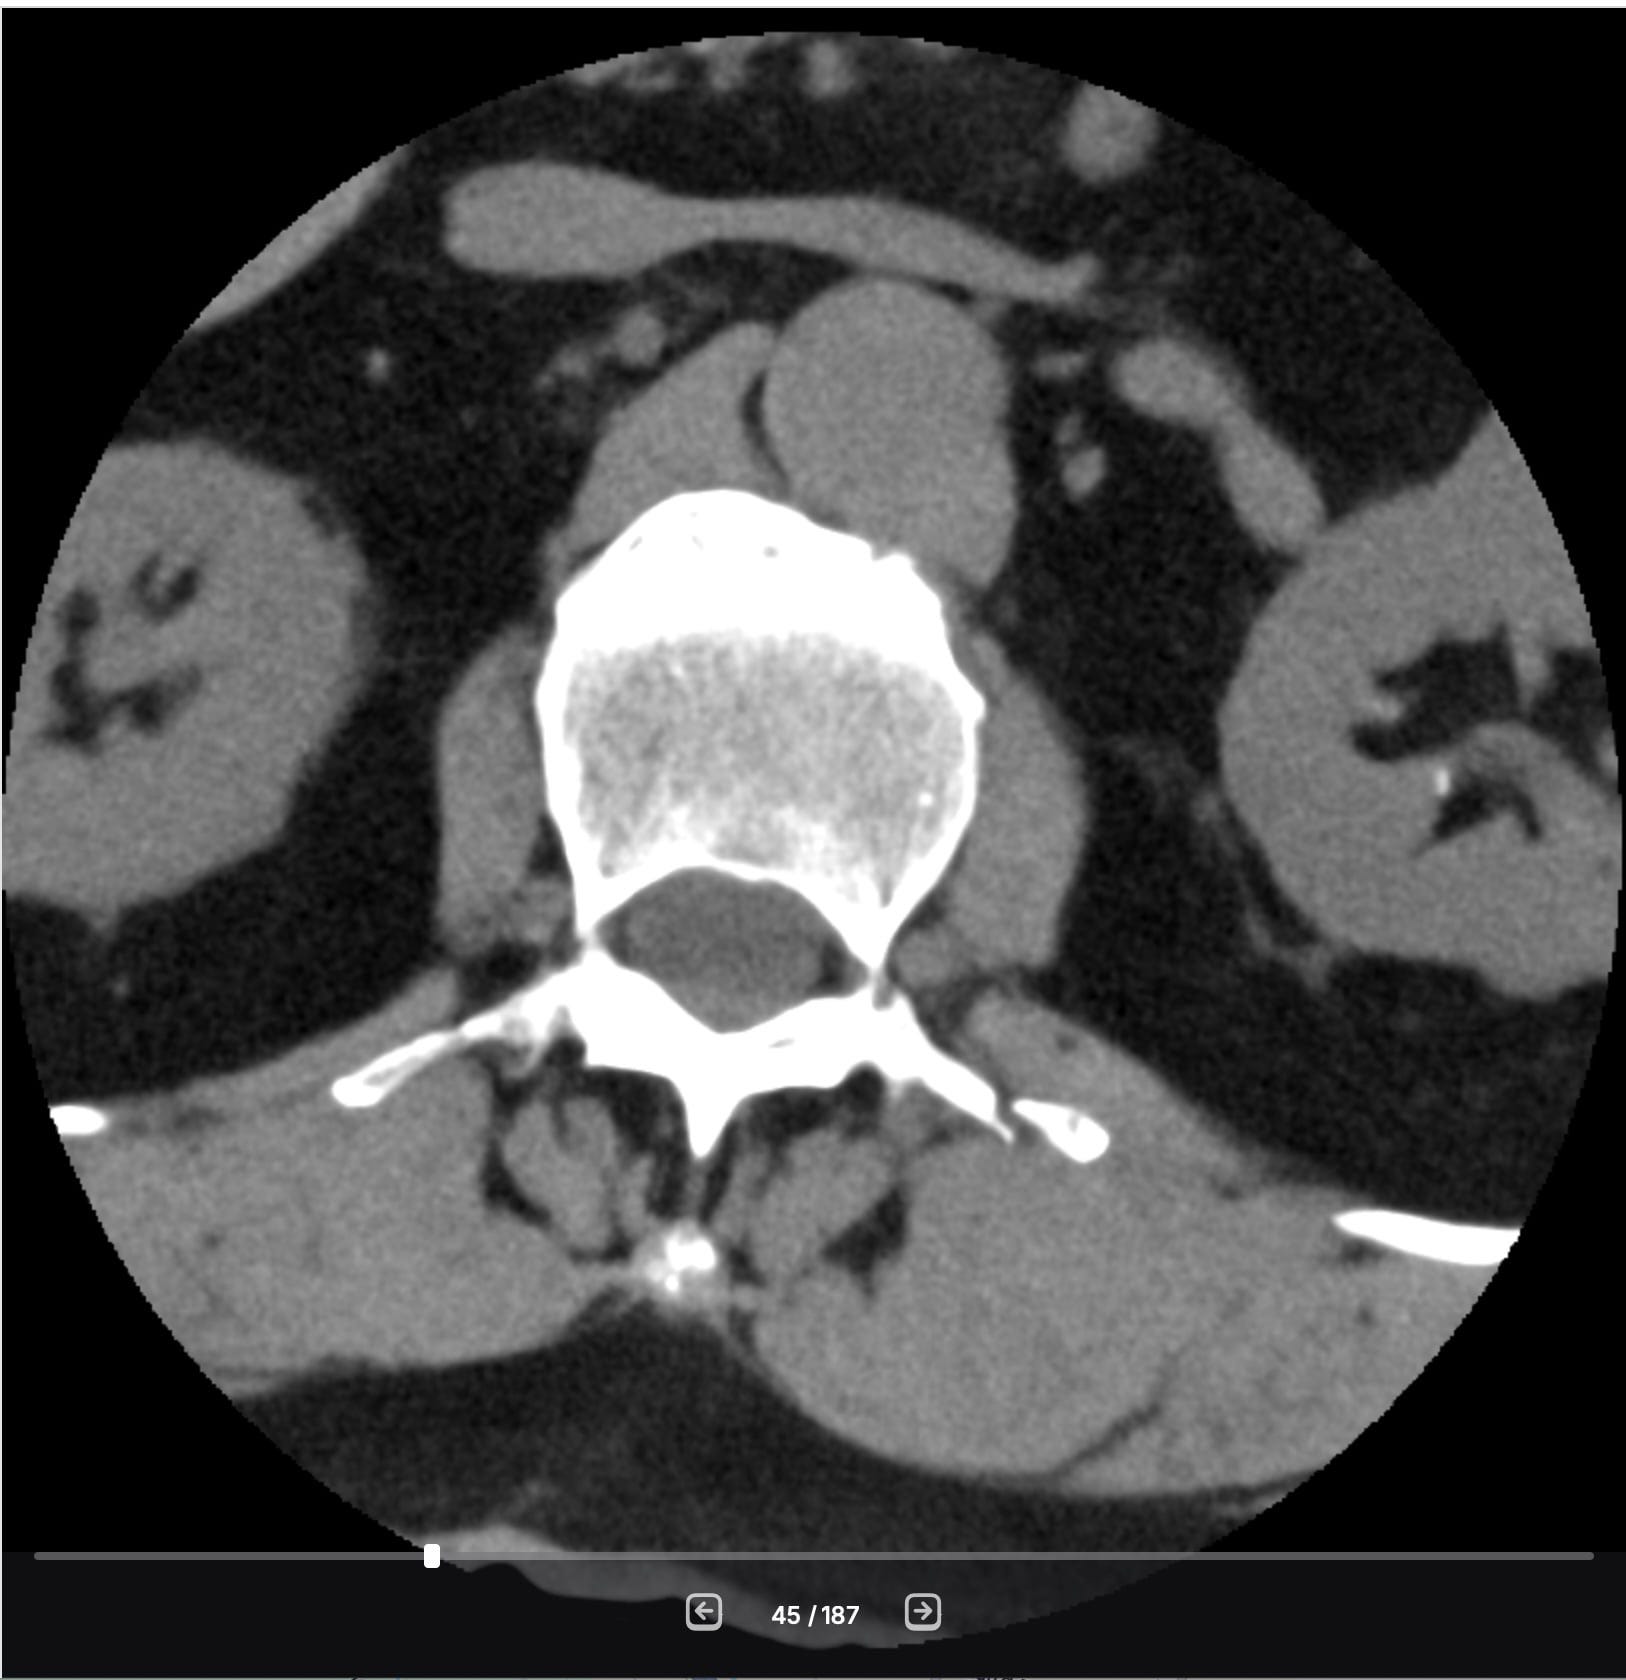

The result was that I suffered 3 small fractures of what are called the transverse processes on my spine. I have images. You can see the break on the right.